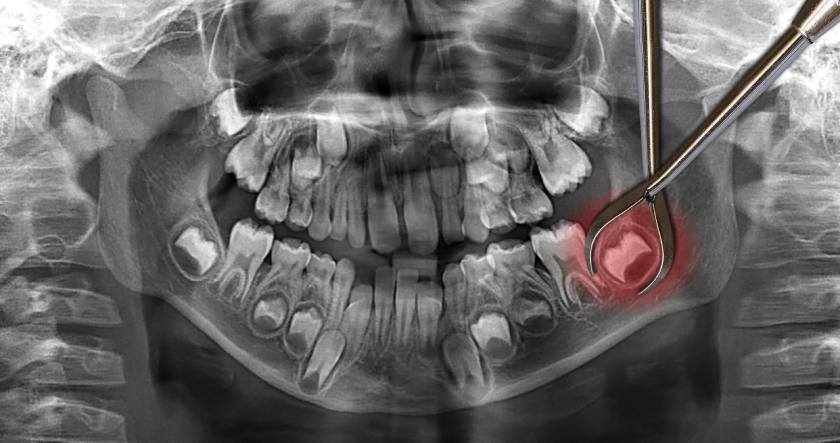

Nếu tình trạng đau nhức kéo dài, bệnh nhân phải đến gặp nha sĩ để chụp phim và xác định chính xác nguyên nhân từ đó bác sĩ mới có thể đưa ra các biện pháp khắc phục phù hợp. Một số cách điều trị viêm lợi trùm răng khôn hiệu quả là:

Trường hợp nướu bị sưng do răng khôn mọc lệch, mọc ngang hoặc mọc ngầm, bác sĩ sẽ chỉ định nhổ răng để đảm bảo an toàn cho những chiếc răng còn lại và hạn chế tối đa những biến chứng nguy hiểm về sau.

*Chụp phim X-Quang hoặc phim 3 chiều CT Cone Beam là một bước quan trọng trong quy trình điều trị phục hồi răng. Vì vậy Khách hàng sẽ được Bác sĩ của nha khoa Nhân Tâm chỉ định đến các cơ sở y tế đủ chức năng để thực hiện trước khi điều trị.